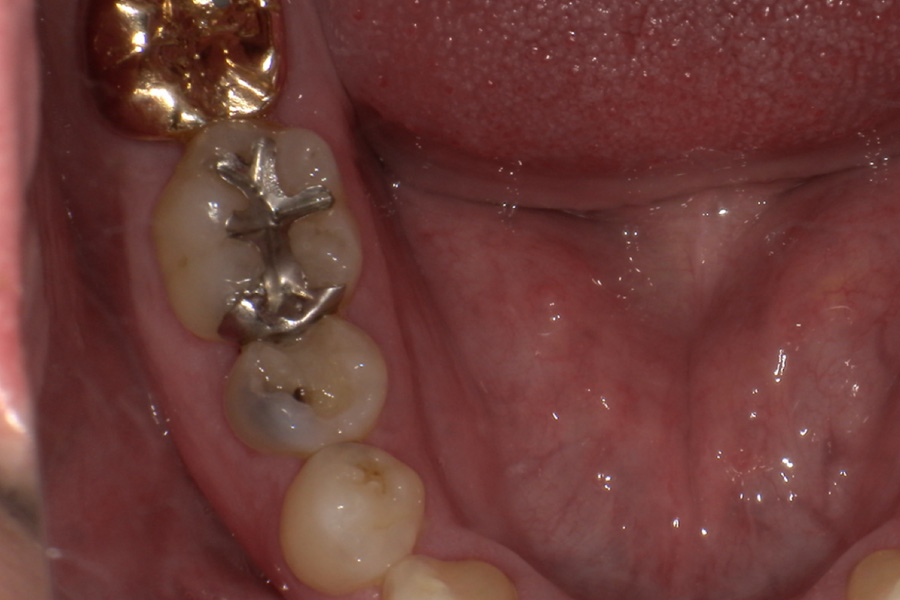

虫歯があるから削ったり悪くなったから抜くのではなく、まずは虫歯と歯周病が起きないようにより良い環境づくりをすること、そうすることによって歯を長く維持することが可能となります。

そのためには、健康状態に関する情報と生活習慣などの状況を把握したうえで、お口の中のリスク評価をおこないます。

その結果をもとに、お一人お一人にあった治療計画をご提案させていただきます。